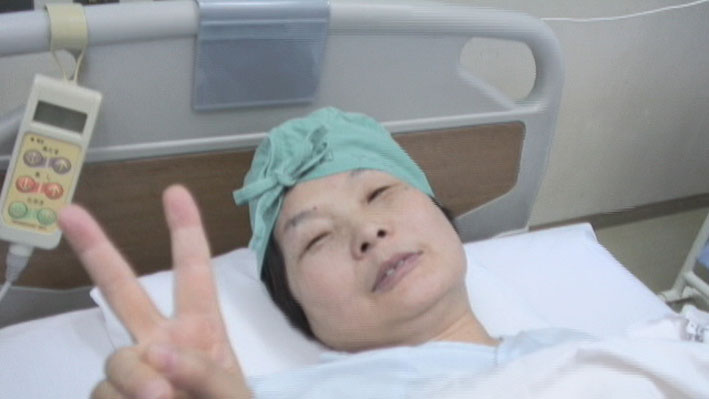

さあ、手術が始まるよ。ピース!

| 10月3日、いよいよ手術の日が来た。 |

「では、これから手術に入ります!」ピース!ピース。 |